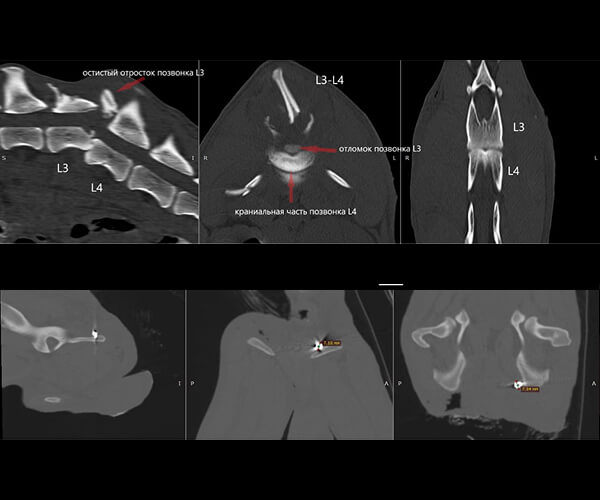

Сейчас в теле щенка застряли пули, повреждён позвоночник и спинной мозг. Он не может лечь, ест и спит только сидя, и каждую минуту терпит боль. Каждая попытка движения, каждый вдох даются ему с трудом. Постоянная боль истощает его силы, лишая надежды. Врачи борются за его жизнь, но состояние Зухрая критическое. Необходимы экстренные меры, чтобы стабилизировать его состояние и предотвратить дальнейшее ухудшение.

Врачи говорят, что полностью восстановить чувствительность уже не получится. Но у Зухрая есть шанс облегчить страдания и прожить жизнь без постоянной боли. Для этого нужны обследования и лечение в Москве. Специализированная клиника в столице располагает необходимым оборудованием и опытными специалистами, которые смогут оказать ему квалифицированную помощь. Каждое обследование, каждая процедура – это шаг к облегчению его страданий, к возможности дышать полной грудью, к возвращению к жизни, пусть и с ограничениями.